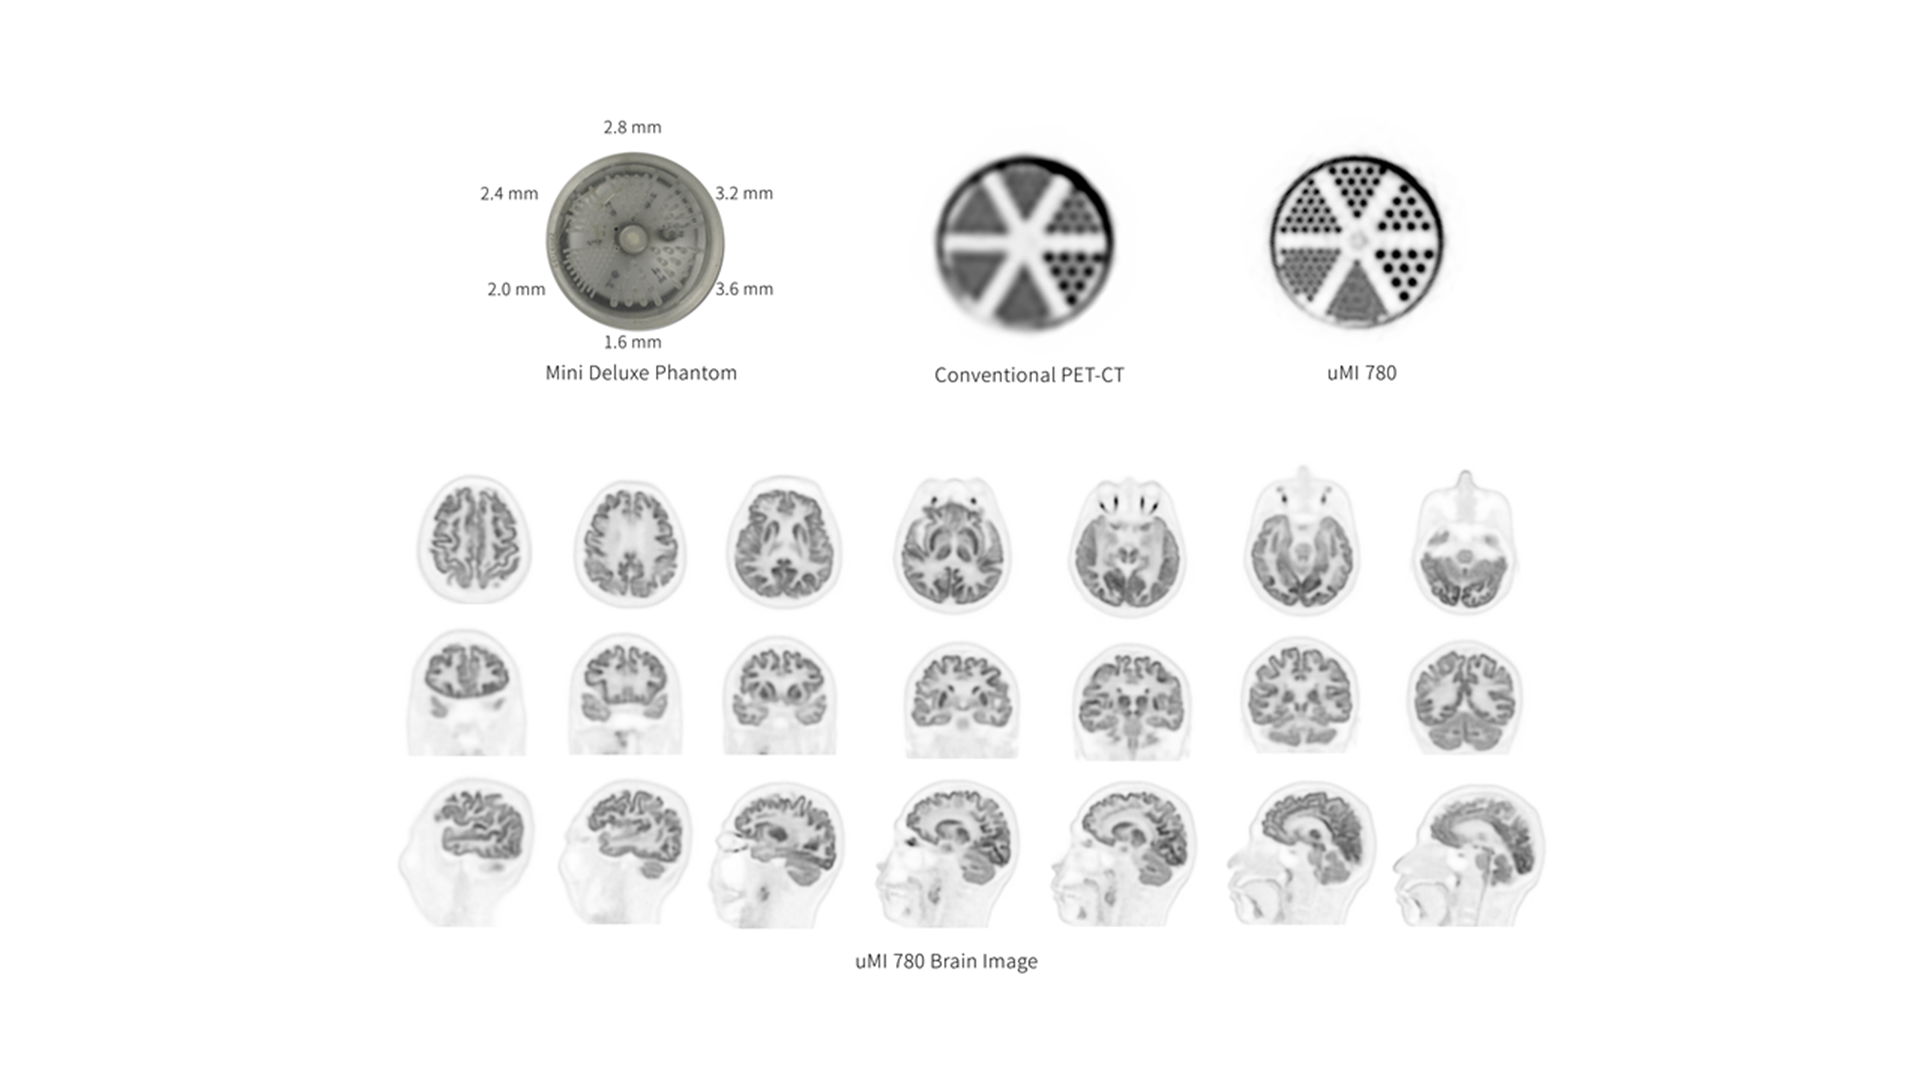

Combining a long axial FOV digital PET with a 160-slice CT, the powerful uMI 780 scanner provides 2.9mm NEMA resolution, 16cps/kBq sensitivity and a 30cm axial FOV for a revolutionary breakthrough in the combination of clarity, sensitivity, coverage and speed.